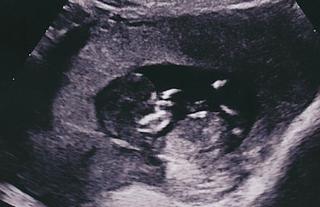

Dievčatá pozrite môj album...Všetko je OK🙂))))))))) krásne to bolo...